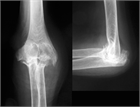

1. 投薬治療抵抗性のリウマチ肘では関節破壊が軽度の場合、滑膜切除術が勧められる(推奨度2)

1. 関節破壊が高度の場合、人工肘関節形成術が勧められる(推奨度3)。ただし、手術手技、後療法に習熟した施設、術者によって行われることが望ましい。